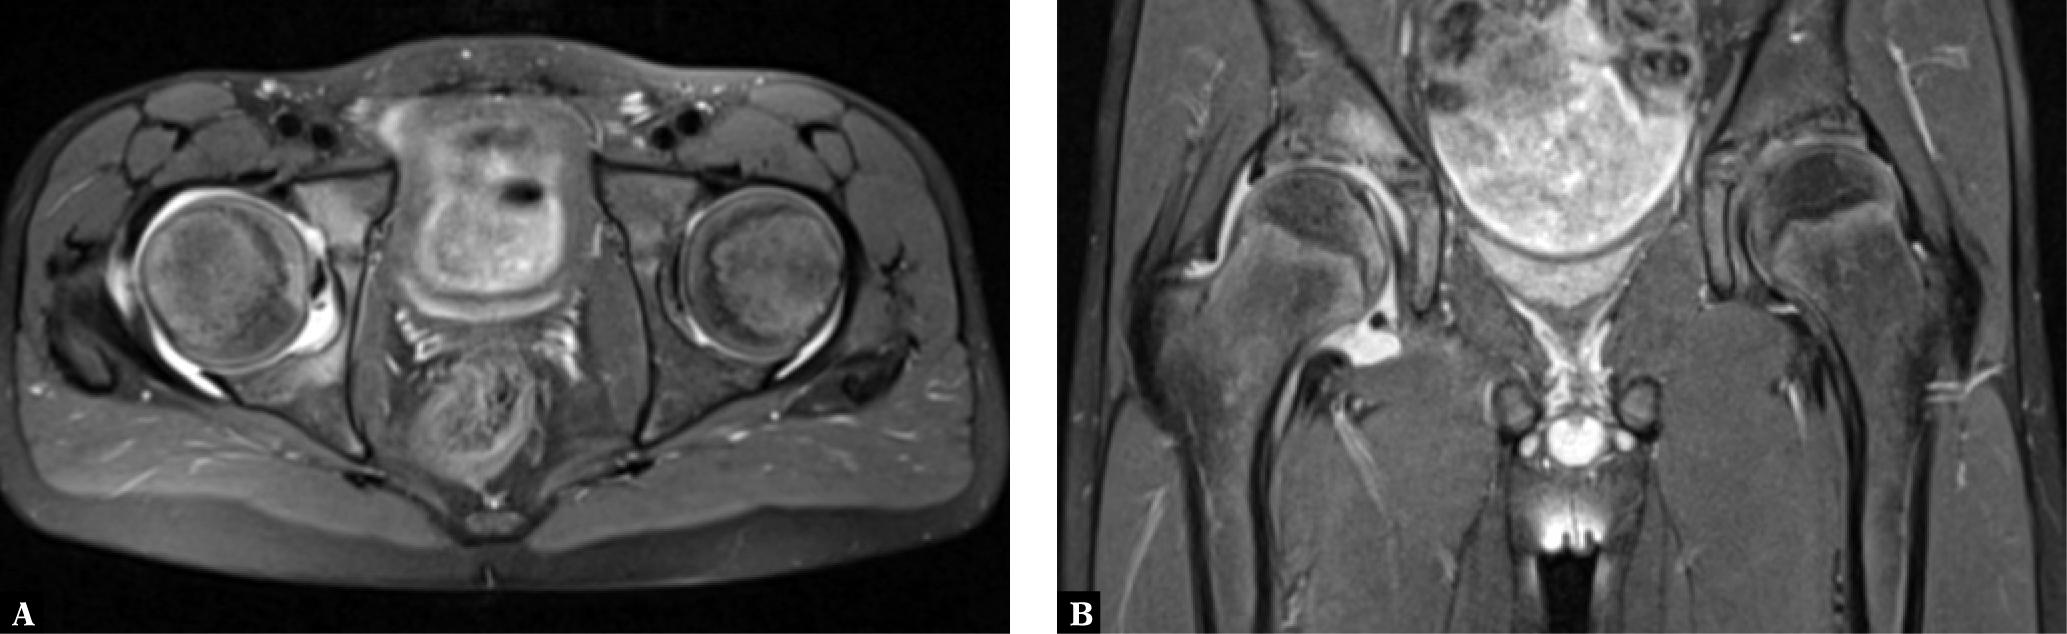

Juvenile psoriatic arthritis (JPsA) is a very peculiar subtype, mostly affecting ANA+ (antinuclear antibodies) girls presenting with dactylitis and peripheral oligo- or polyarthritis at disease onset. The radiographic changes seen in children with this disease differ from those observed in adults because sacroiliitis and spondylitis are rare, and the full gamut of radiographic changes of adult PsA is unusual in children(29,30). Like in JAS, the disease usually begins with monoarthritis, often of the knee joint, or oligoarthritis. Later in the disease course JPsA progresses to oligo- or polyarthritis, with asymmetrical changes of joints in the upper and lower extremities. The mean age of onset of this disease is 9 to 10 years, and girls are primarily affected (2.5:1 ratio)(16).

Initially the radiographic image is normal or shows thickening of periarticular soft tissue and periarticular osteoporosis. Like in adults with PsA, radiographs may show periosteal thickening (periostitis) along the shafts of the phalanges and the metacarpal and metatarsal bones. In addition, acro-osteolysis of the nail tuberosity, and distal interphalangeal joint (DIP) involvement with concomitant destruction (cysts and erosions) and proliferative bony lesions may be seen. Eventually, osteolysis and ankylosis may occur(29,31). However, DIP joint changes, which are characteristic of late stage adult PsA, are uncommon in children(17,29).

Thickening and increased density of the finger or toe soft tissues represent dactylitis, or the „sausage finger or toe,” reflecting flexor tenosynovitis and/or edema of the soft tissues along with synovitis (Fig. 5). Tenosynovitis and synovitis are well seen on US and MRI, like in adults with PsA(29). Finally, as in JAS, enthesopathic changes in JPsA could be the only abnormal finding(30).

Clinical and ultrasound images in a 12-year-old girl with JPsA: A. “sausage toe” 2 and 3 of the right foot; B. a US in a transverse view shows active synovitis in the MTP 2 and 3 joints; C. a longitudinal scan shows tenosynovitis of the long flexor of the 2nd toe and tendititis secondary to tenosynovitis seen in color Doppler US

Sacroiliitis may be unilateral and resemble reactive arthritis(17). Spondylitis rarely leads to subluxation in C1/C2 in children; syndesmophytes or parasyndesmophytes, which are typical of adults with PsA, are also seen rarely in children(29,32).